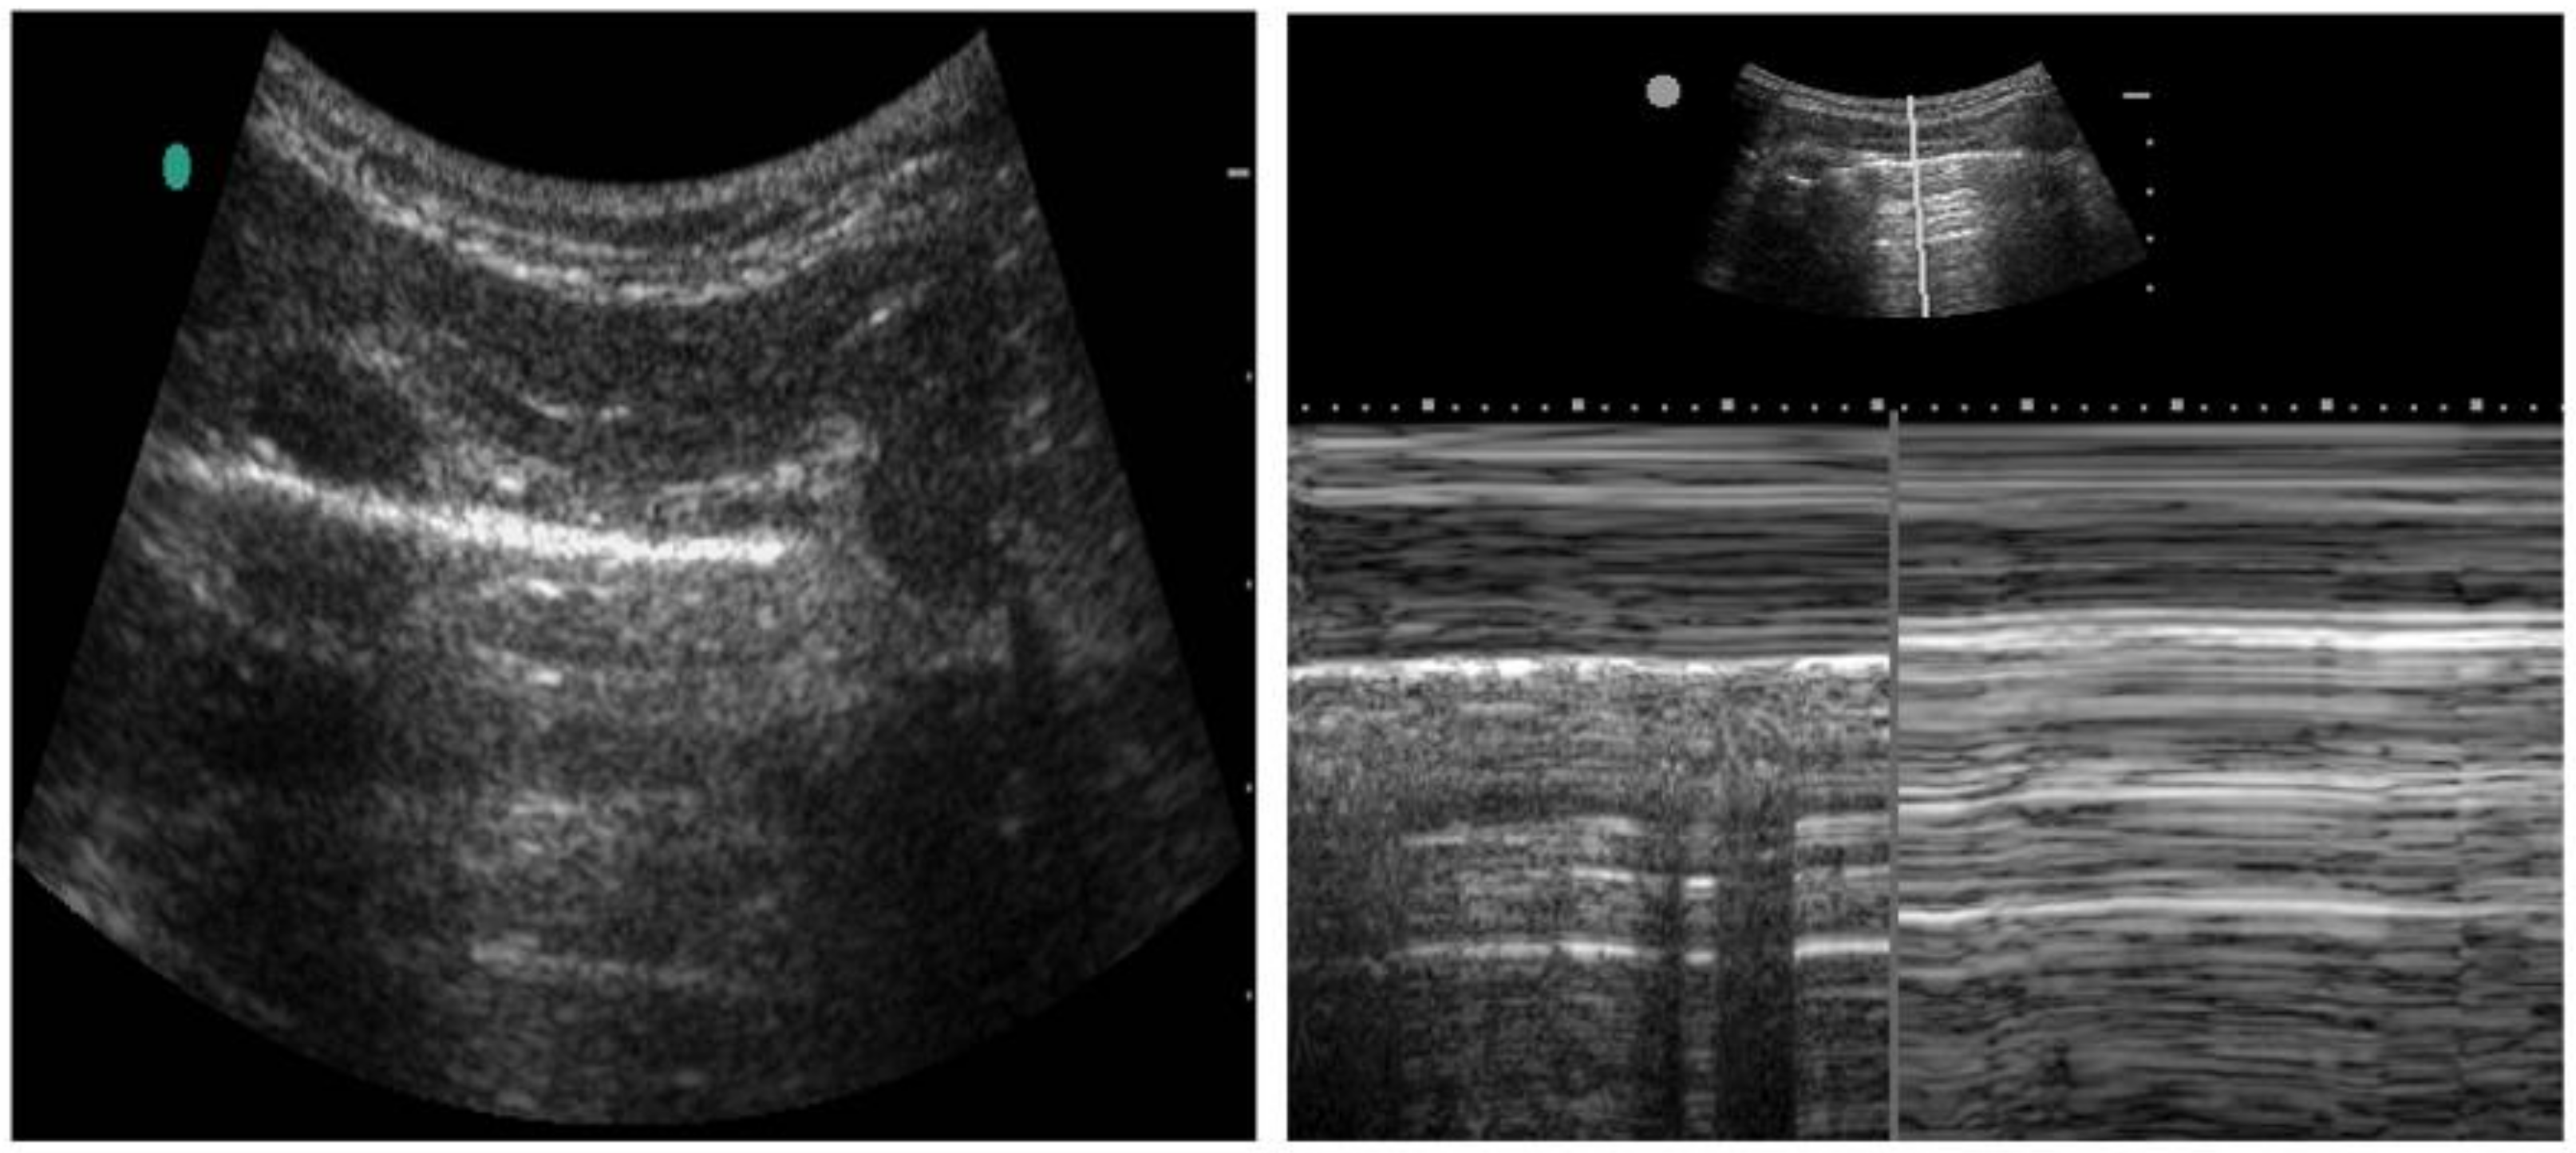

2.3. Thoracic Ultrasound